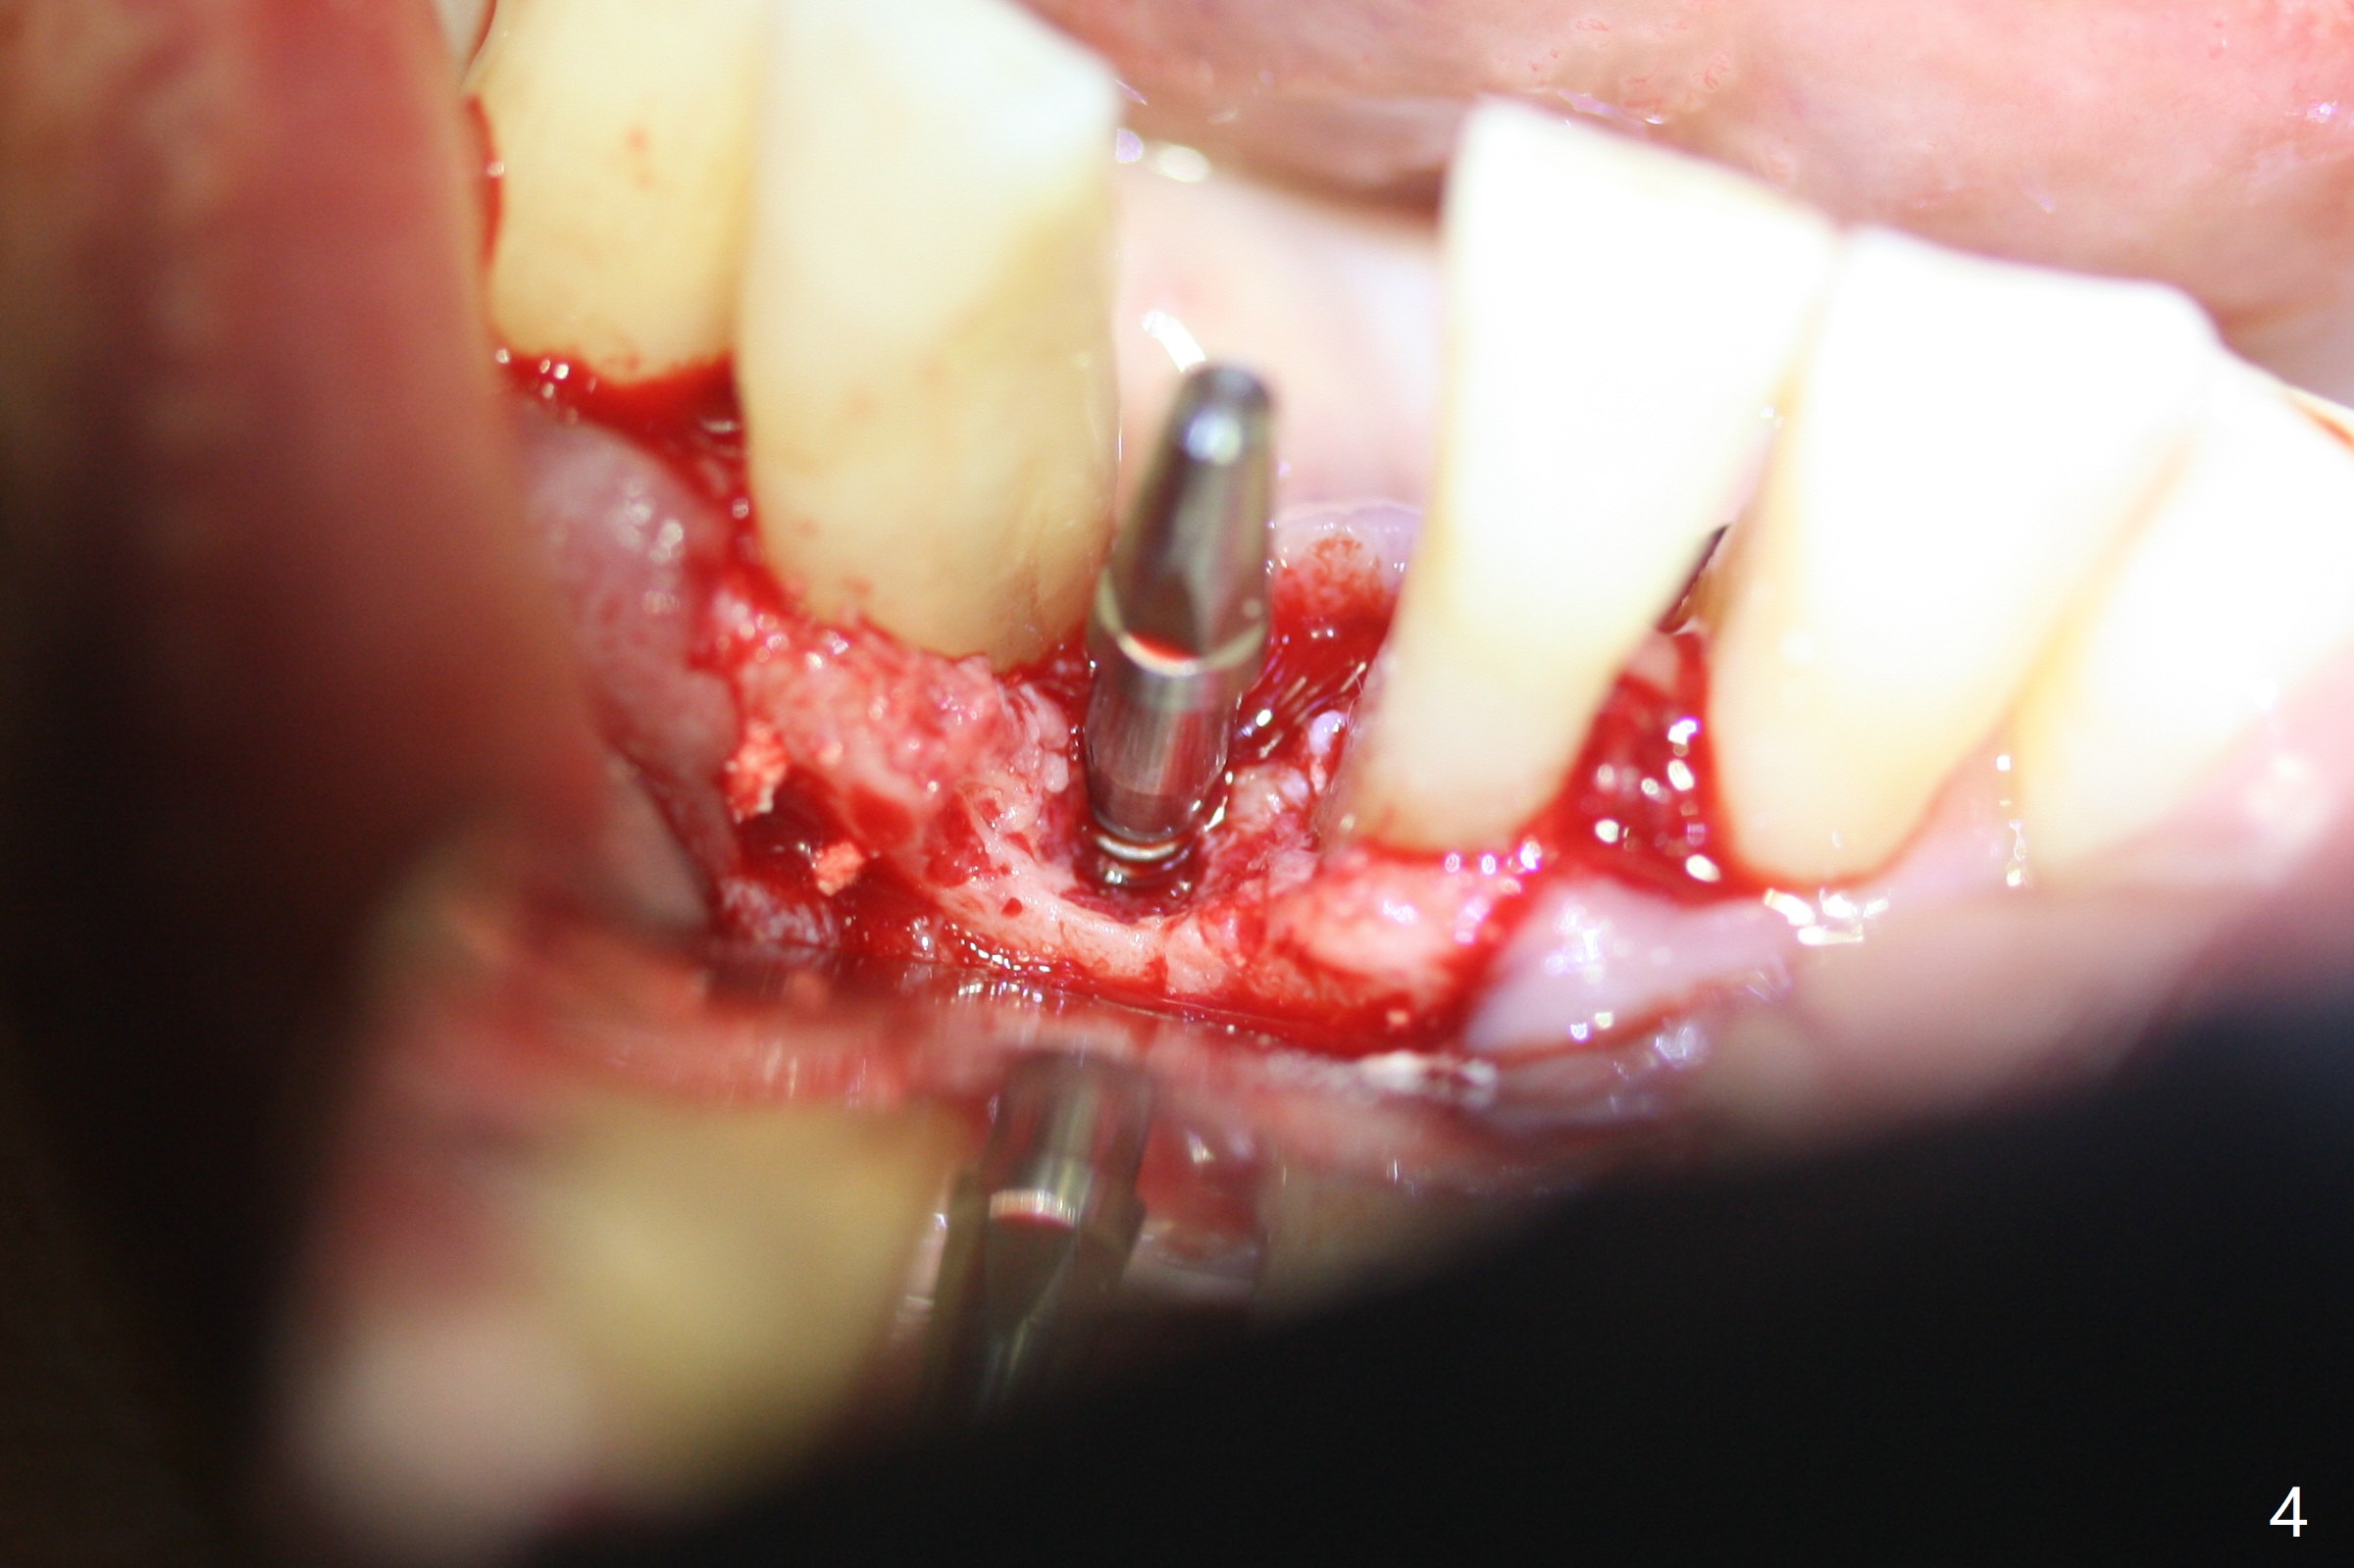

Implant

Out of financial concern, the patient does not agree to have the tooth #26 extracted. Due to atrophy of the most coronal ridge buccally at #25 (Fig.1,2 *), osteotomy is initiated difficult and distal (Fig.3). After 1.2 mm drill removal (Fig.3' black area), Lindamann bur is used to move the osteotomy mesial (red area). A 2x12(4) mm 1-piece implant is placed (Fig.4,5); the buccal defect is packed with allograft (Vanilla, .5-1 mm cancellous/cortical mixture, *). When the tooth #26 fails, a 2 mm implant will be placed (Fig.6 blue). Following abutment adjustment, a provisional is fabricated (Fig.7 P); note the lower incisal edges of #25 and 26, as compared to those of the neighboring teeth. To reduce occlusal trauma, the incisal edge of the tooth #26 has been decreased (Fig.5 open arrow). The implant threads seem not to be exposed 4 months postop (Fig.8), although the tooth #26 has mobility II.